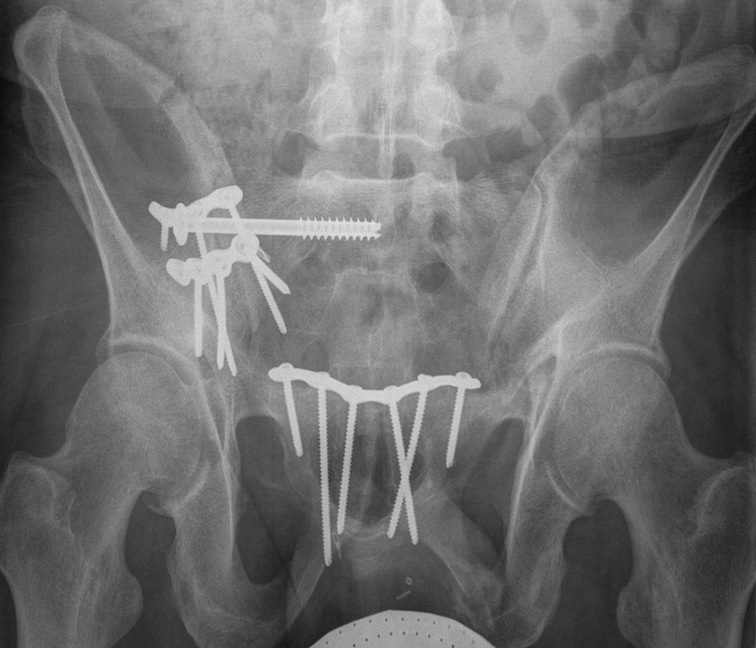

Posterior fixation

Percutaneous sacroiliac screws

Posterior approach + / - plates

Posterior sacral plates

Technique

- patient prone

- vertical incision 1 cm lateral to PSIS

- from crest to sciatic notch

- incise and reflect G maximus

- apply transverse plate

- soft tissue can be a problem

Anterior fixation

Indications

- instability following posterior fixation

- bilateral pubic rami fractures

Options

- plate - modified stoppa

- percutaneous ramus screws

- external fixation

LC-1 with anterior external fixation Plating of bilateral pubic rami fractures